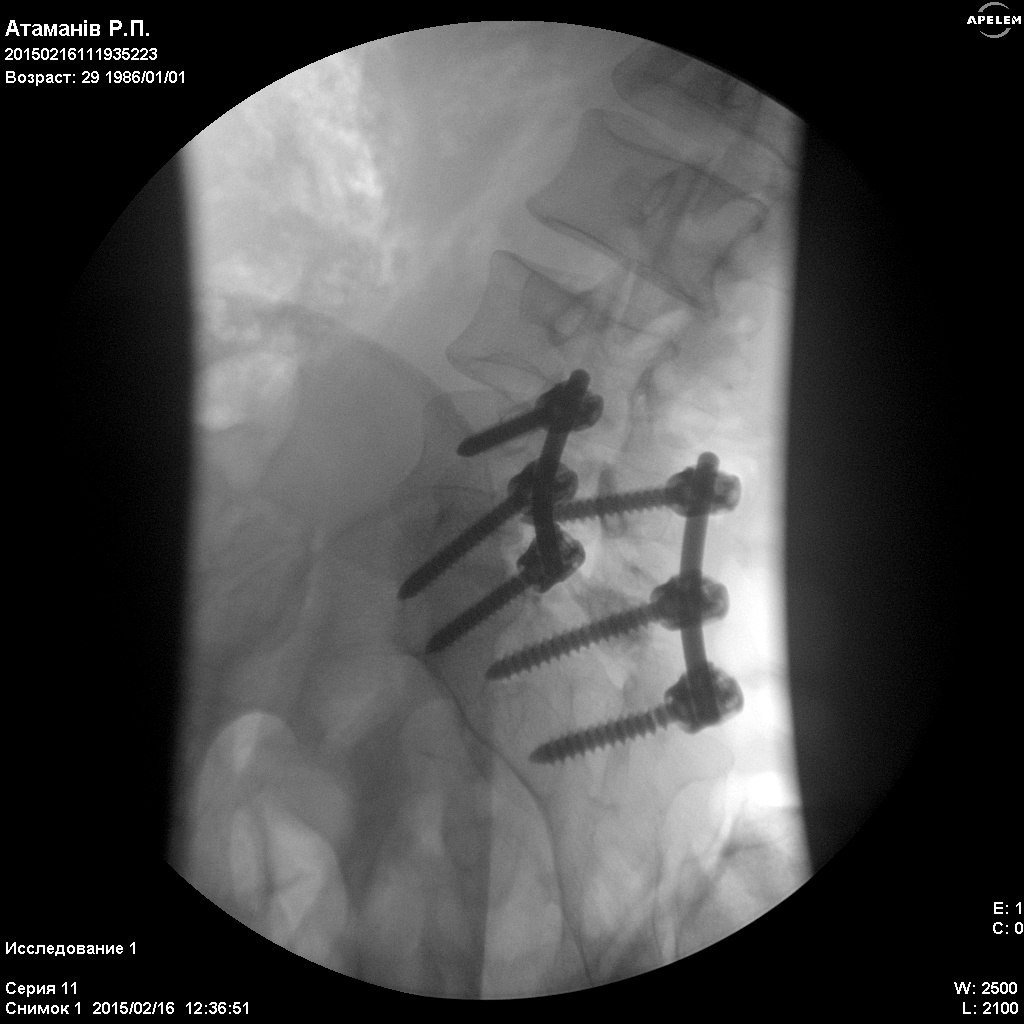

У Харківському державному інституті патології хребта і суглобів ім. проф. М.І. Сітенка, Сергію зробили операцію відкритого вправлення Л5 хребця. Та провели стабілізацію на рівні Л4,Л5-С1, конструкцією "медтронік". Тобто йому зафіксували хребет за допомогою металевих з'єднань.

"На операцію витратили 100 000 гривень. Але, на жаль, конструкція не витримала навантаження хребта і ситуація значно погіршилась. Хлопець прикований до ліжка. Кожен може допомогти йому побороти хворобу. Нині потрібна повторна операція, на яку необхідно зібрати ще 100 000 гривень до кінця березня. Батьки вичерпали всі свої збереження, і самі справитись з цим горем не в стилі. Вони благають про допомогу небайдужих. Батько Сергія захищає нас в АТО від окупації ворогів. Мати має 3-тю групу інвалідності, поліартрит. Тому зібрати потрібну кількість грошей не вдається", - пише Ірина.